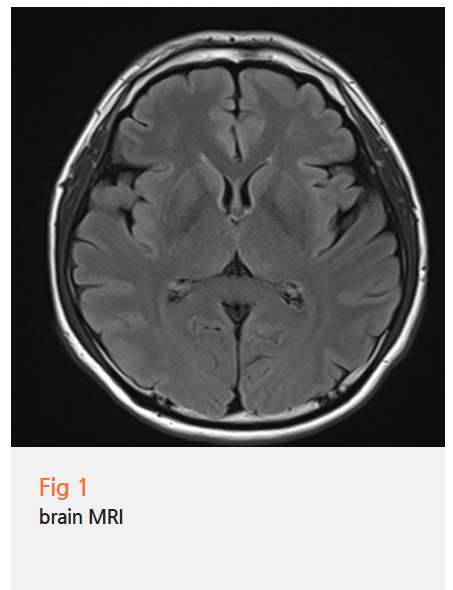

처음엔 심각한 뇌 질환이라고 생각하고

뇌 MRI까지 찍어봤지만 매번 '이상 없음' 결과만... ㅠㅠ

환자분들이 어지러움을 호소하면

대부분 뇌 질환부터 의심하게 되니까,

뇌 MRI나 CT를 먼저 찍어보게 되는데...

정작 목디스크가 원인일 가능성은 놓치는 경우가 정말 많거든요.